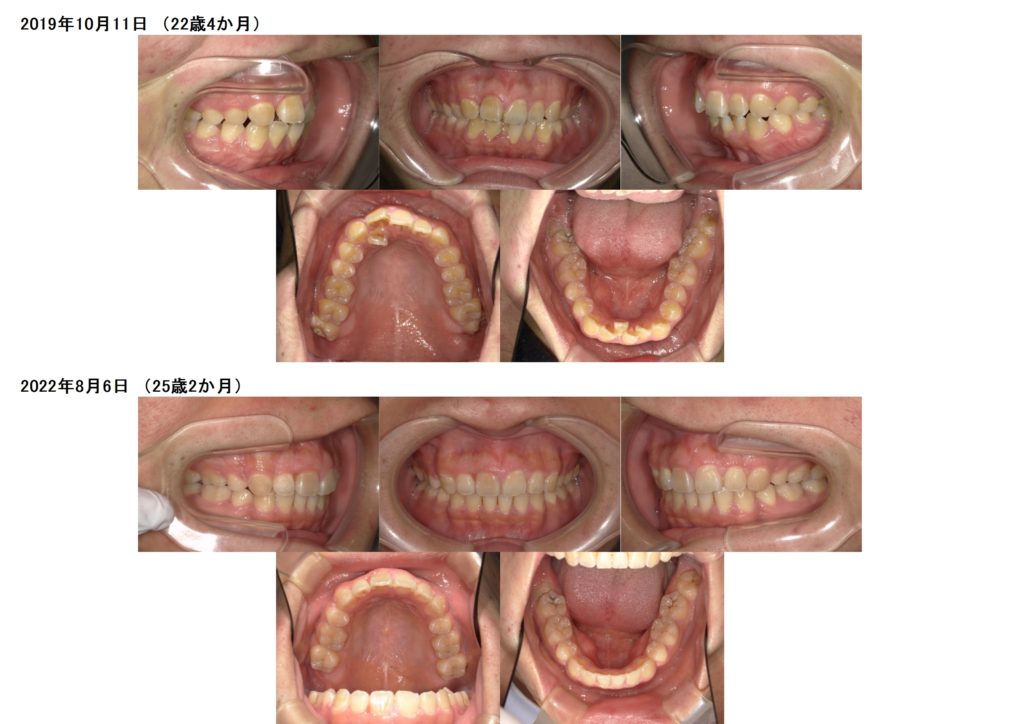

今回は マウスピースを使用し上下抜歯の治療例です。

この患者様は上下4番目の歯を抜歯してマウスピースにて治療をしました。

とってもキレイになりましたよね☺

また、ここからリテーナーと呼ばれる保定装置を使用し乱れてこないように保定をさせていただきます。

もうしばらくマウスピースの使用をしていただきますが、アタッチメントが無くなるだけで、とってもスッキリしますよね!!